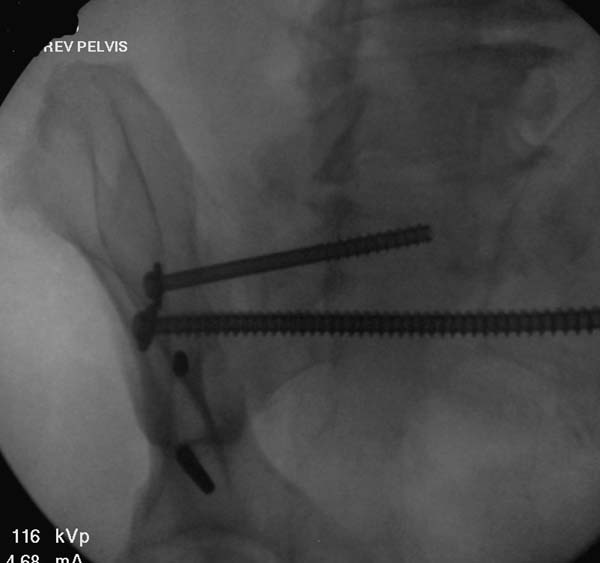

Здесь снимки, которые показывают направление стержня, а также идею

репозиции вытяжением. На рентгенопроницаемых столах имеется возможность

установить дополнительную раму, где по желанию можно увеличить или

уменьшить высоту угла вытяжения. Для репозиции таза больной в положение

на спине, стержень для вытяжения остается во время операции. Система

подойдет для тракции головки бедра из вертлужной впадины, и для этого

стерильная веревка и Synthes Universal Chuck with T-Handle.

Двухстороннее повреждение крестца и травматическая ампутация бедра, где

неопытной бригадой дежурантов установлен верхний наружный фиксатор для

стабилизации. На третий день ревизия на более стабильный, и

окончательная фиксация. Первые снимки после стабилизации таза, и другие,

где показаны (параллельные) правильная установка на AIIS т.е на месте

прикрепления прямой мышцы бедра. Ампутация закончена костно пластическим

методом.